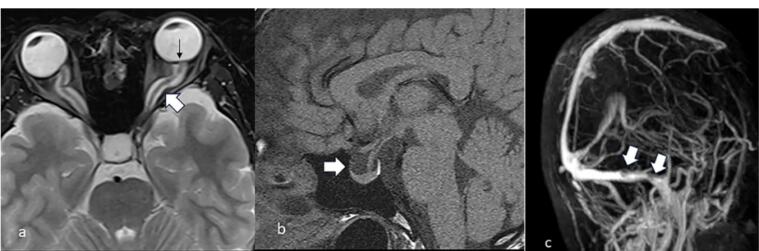

Idiopathic Intracranial Hypertension.